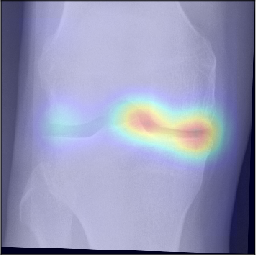

To gain insight into the basis of the CNN’s prediction, we used the GradCAM [24] approach and visualized the attention maps for the well-predicted knees. Examples of attention maps are presented in Figure 5. We observed that in various cases, the CNN paid attention to the compartment opposite to the one where degenerative change became visible during the follow-up visits. Additional examples of such attention maps are presented in Supplementary Figures 3, 4, 5 and 6.

Refer to caption

(a)

(b)

(c)

(d)

Figure 5: Examples of attention maps for progression cases and the corresponding visualization of progression derived using follow-up images from MOST datasets. Here, subplots (a) and (c) show the attention maps derived using a GradCAM approach. Subplots (b) and (d) show the joint-space areas from all the follow-up images (baseline to 84 months). Here, the subplot (b) corresponds to the attention map a) and the subplot (d) corresponds to the attention map (c).